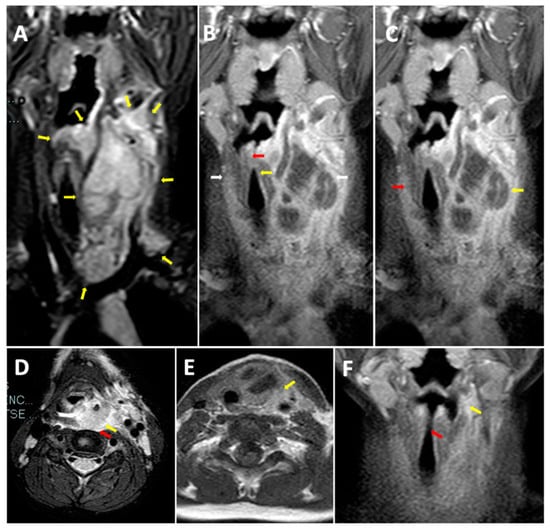

- Han, Z.; Tai, J.; Gao, J.; Wang, S.; Yu, T.; Peng, Y.; Ni, X. MRI in Children With Pyriform Sinus Fistula. J. Magn. Reson. Imaging 2021, 53, 85–95. [Google Scholar] [CrossRef] [PubMed]

- Chen, T.; Ge, G.; Chen, J.; Zhao, X.; Sheng, Q.; Zhu, L.; Xu, W.; Liu, J.; Lv, Z. Pyriform Sinus Fistula in Children: Preferred Imaging Modality and Risk Factors for Diagnostic Delay. Front. Pediatr. 2020, 8, 575812. [Google Scholar] [CrossRef] [PubMed]